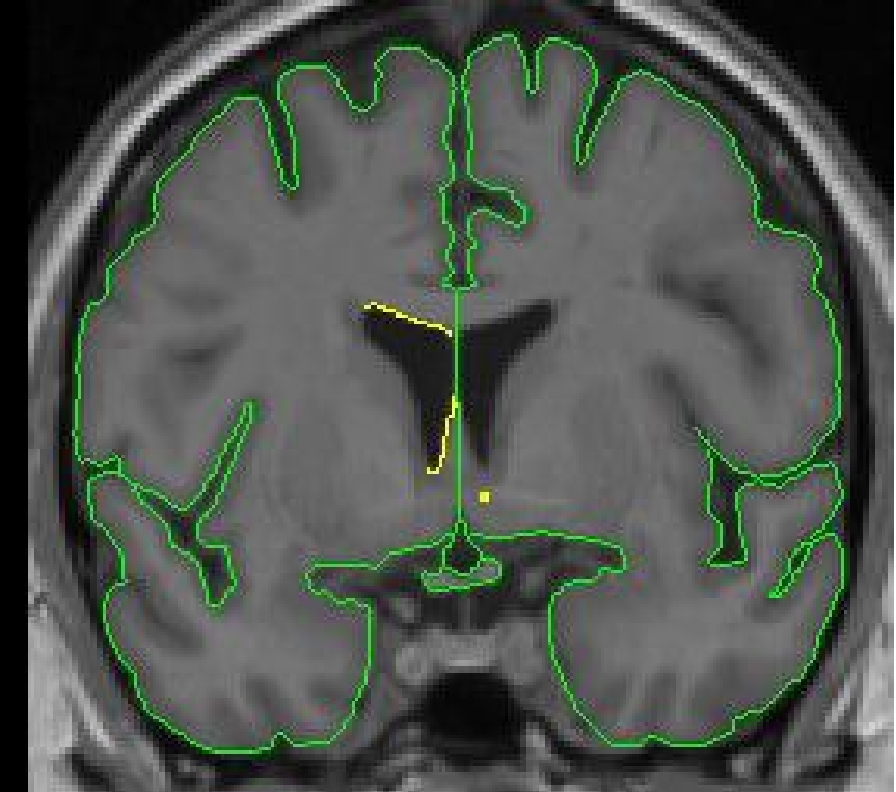

When the caudate is present two histograms are needed to define the two different

borders of the ventricle.

5. You may need to manually connect your "saved" contour to the new

contour. By convention, in cases in which the caudate is present, include the

most inferior extent of the CSF/white matter border as the lateral ventricle

border, even if that necessitates drawing a short line from it to the CSF/gray matter

border.